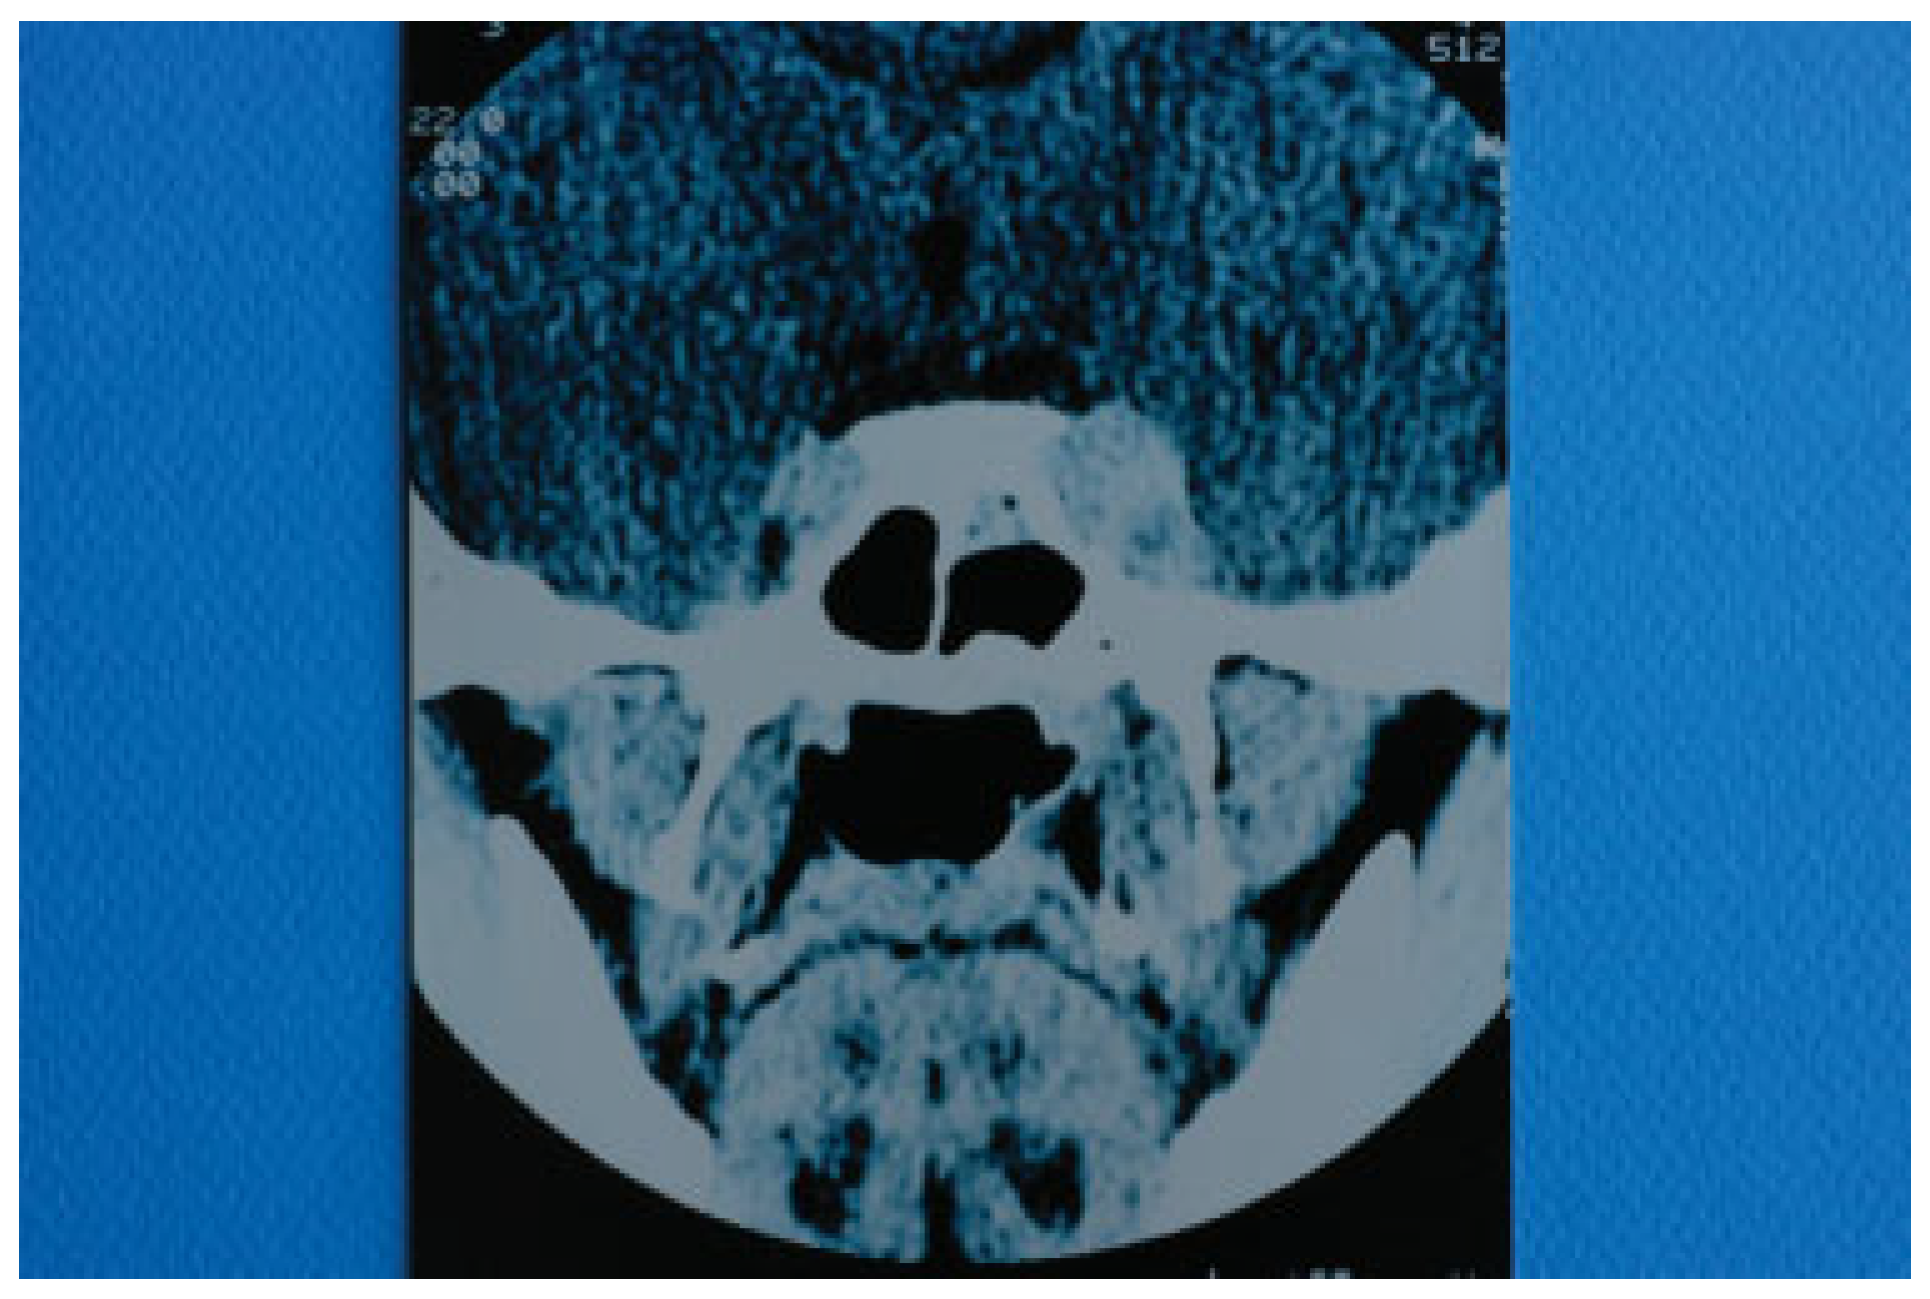

On the 21st postoperative day (31st postinjury day), the patient presented with marked left exophthalmos, periorbital swelling and ecchymosis, ptosis of the upper eyelid, ocular pain, nausea, and vomiting. The condition was diagnosed as periorbital cellulitis and double intravenous antibiotic therapy was initiated (Figure 2). Computerized tomography (CT) of the left orbit disclosed a mild inflammatory reaction around the miniplate in the infraorbital rim and in the region of the orbital floor. CT also revealed the presence of dilation of the upper ophthalmic vein but this finding was not further evaluated at that time (Figure 3). The clinical presentation of the patient was attributed to infection of foreign materials that were placed during the operation and therefore the plate and the lyophilized dura were removed.

Two days after the removal of the foreign materials, there was a dramatic deterioration of the patient’s clinical presentation with intense ocular pain, worsening of exophthalmos, nausea, and vomiting. The patient also complained of “strange sounds in the cranium like water tapping.” Clinical examination revealed a systolic thrill on palpation of the left eye and a systolic wheeze on auscultation of the left frontal and temporal area. Measurement of intraocular pressure was subsequently performed and an intraocular pressure of 13 mm Hg in the right and 24 mm Hg in the left eye were recorded. Visual acuity was measured 5/6 vision and fundus examination revealed venous dilatation without further pathologic signs. The finding of intensive dilation of the left upper ophthalmic vein in the primary computed tomography was reevaluated and a posttraumatic CCF was suspected and included in the differential diagnosis. A new CT of the left orbit was ordered which revealed a threefold dilation of the cavernous sinus (Figure 4). The digital subtraction angiography (DSA) confirmed the diagnosis of CCF as it revealed a dilation of the cavernous sinus, a blood shunt between the lumen of the internal carotid artery and the cavity of the cavernous sinus, and a dilation of the upper ophthalmic vein (Figure 5).

Figure 3. Computed tomography of the skull taken with intravenous contrast medium. Dilation of left superior ophthalmic vein is depicted.